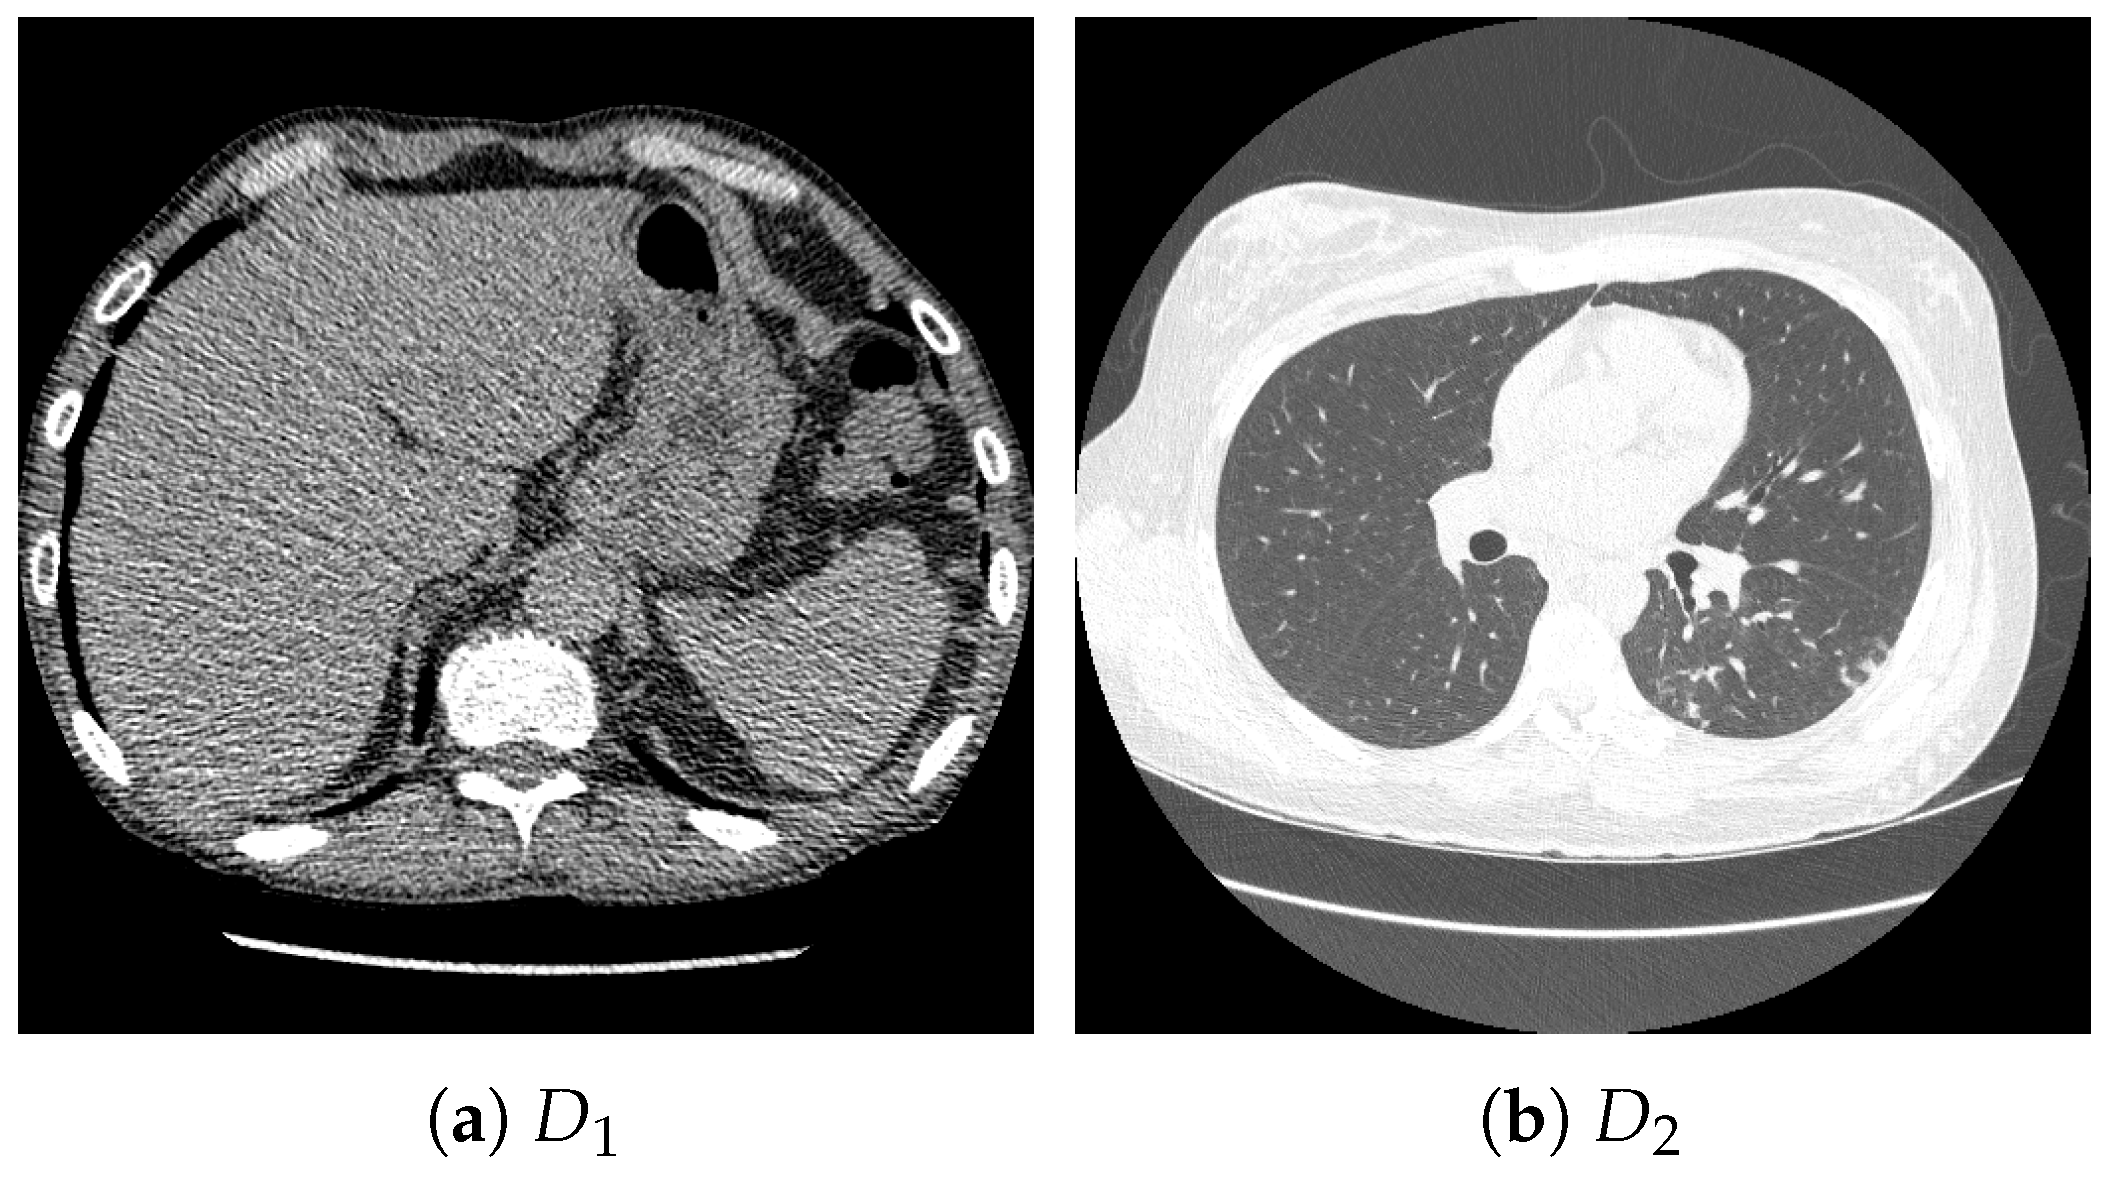

4.1. Datasets and Settings